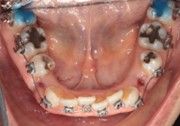

The right side shows a full C-bend from cinching too far from the bracket, then re-bending with a regular Hammerhead plier from a different brand.

The right side shows the distortion produced while bending with a regular Hammerhead plier from a different brand.

The right side has an acute (distorted) bend after bending the wire with a regular Hammerhead plier from a different brand.